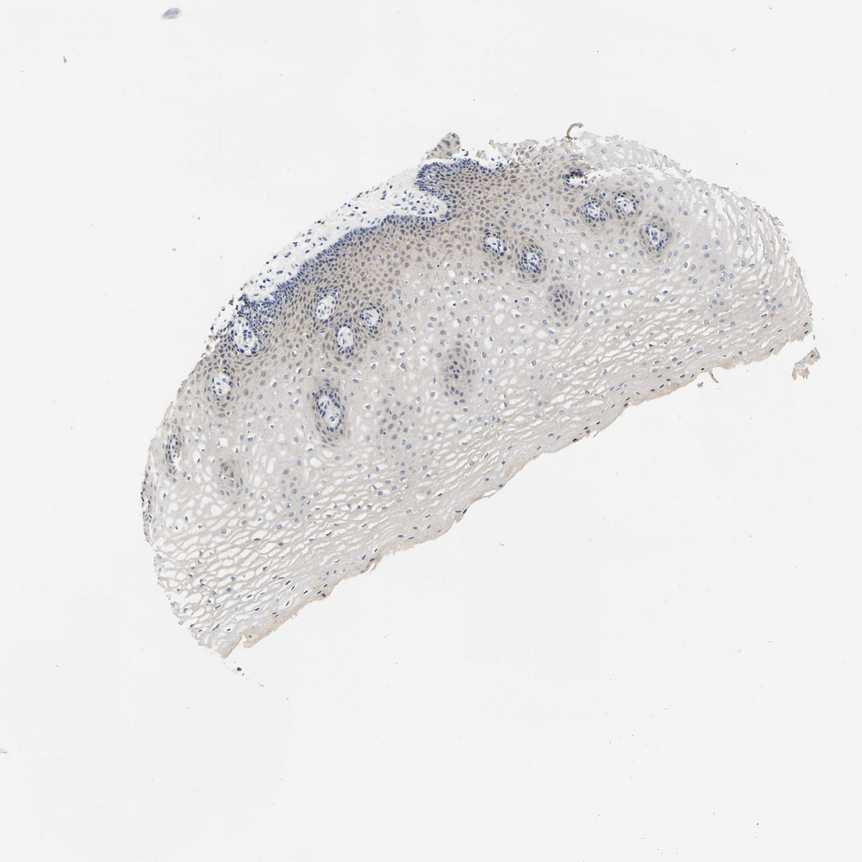

ESOPHAGUS - Antibody stainingi

Antibody staining in the annotated cell types in the current human tissue is reported as not detected, low, medium, or high, based on conventional immunohistochemistry profiling in selected tissues. This score is based on the combination of the staining intensity and fraction of stained cells.

Each image is clickable and will lead to virtual microscopy that enables deeper exploration of all samples and also displays staining intensity scores, fraction scores and subcellular localization as well as patient and tissue information for each sample.

Antibody HPA019049Antibody HPA019051

Squamous epithelial cells Not detectedMedium